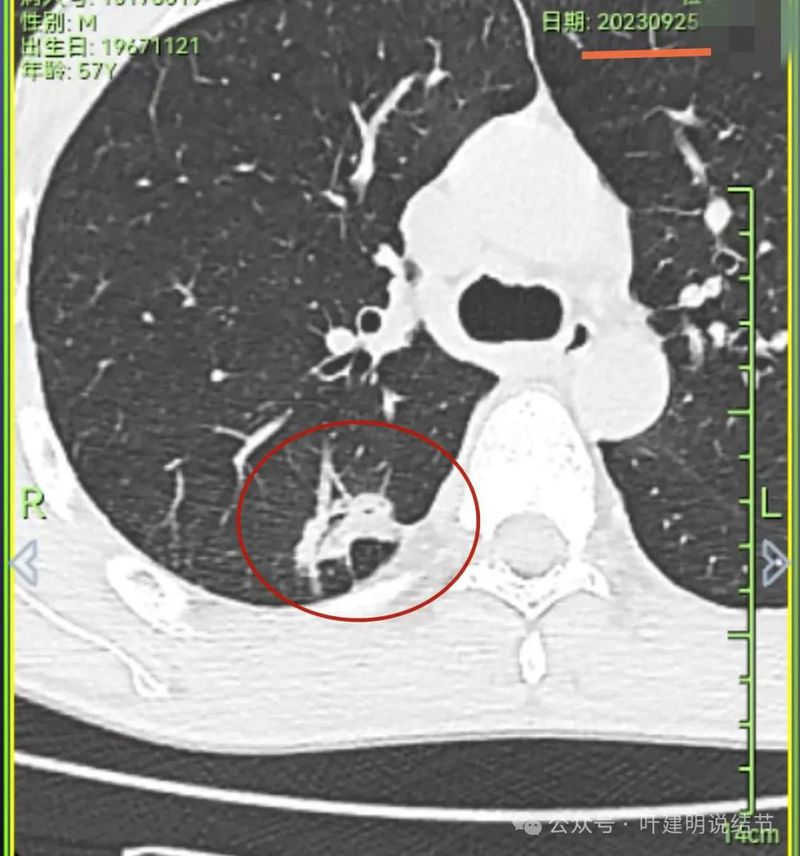

到2023年9月病灶较前进展,或许测量大小变化不明显,但实性成分明显多起来,内部不太致密的部分明显显得较之前密了。